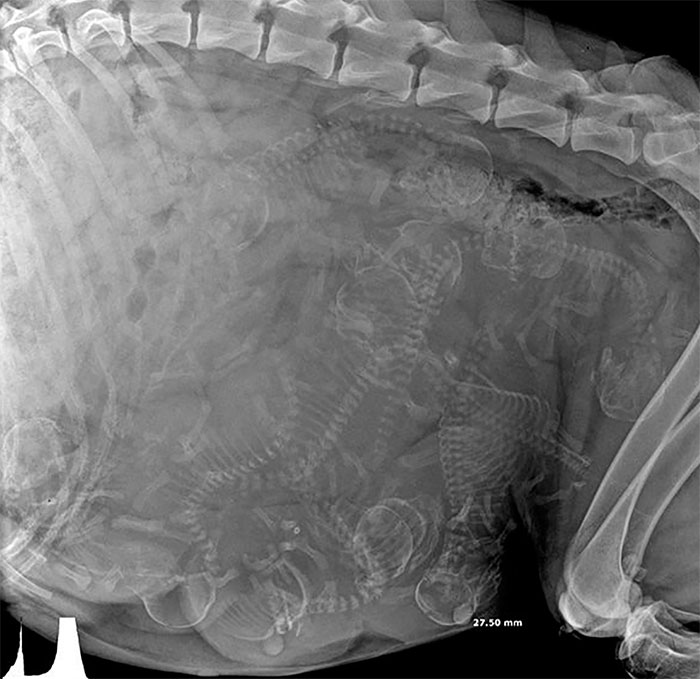

1. En röntgenbild av en gravid hund. Visst ser det lite trångt ut där inne?